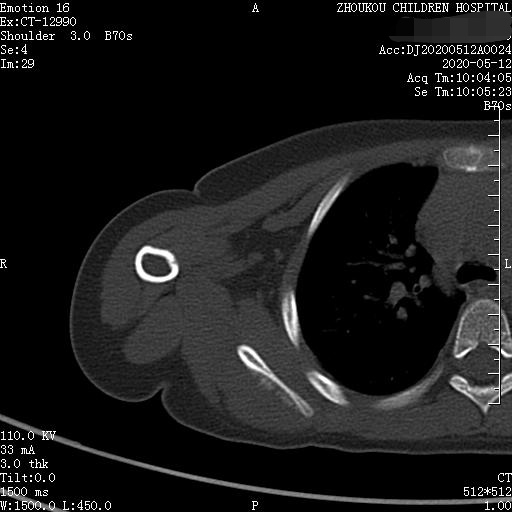

3岁女童以突发右侧肩胛部肿物来院检查,病人无发热、感冒症状,拍右肩关节正位片示:右侧肩关节肩胛岗上缘骨质密度欠均匀,建议CT进一步检查。

通过CT平扫发现:右侧肩胛骨骨质密度不均,骨质内可见“虫食样”低密度影,骨质边缘可见多发放射状骨针,呈“日光射线征”。周围软组织明显肿胀,肌间隙模糊。CT检查意见:考虑:右肩胛骨占位,骨肉瘤可能,不除外其它恶性肿瘤病变,请结合临床及相关检查注意复查。 影像鉴别诊断:骨肉瘤是指起源于骨间叶组织,遗留形成骨细胞直接形成骨样组织为特征的恶性肿瘤,是比较常见的骨恶性肿瘤,好发于十到二十岁青少年,骨肉瘤常见于管状骨,股骨远端胫骨近端最多见,表现为疼痛局部肿胀运动障碍,实验室检查都有碱性磷酸酶升高。